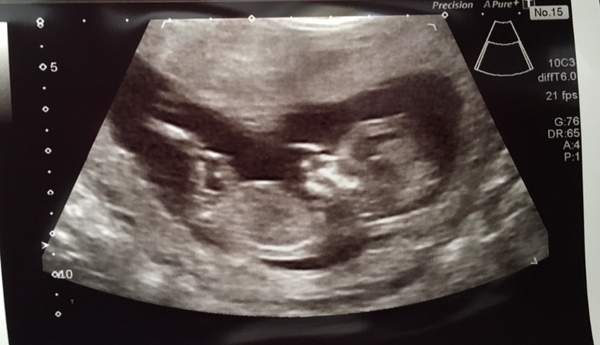

In other news we’ve made it to 13 weeks! Had a scan yesterday and baby was trying to fight the probe thing. It was not happy to be prodded and poked at all. It did not stop wriggling. They couldn’t get measurements for the combined test so I’ve got to go back for bloods but she said all looked ok.

Congratulations @MisBit1 - the first of us to graduate the dreaded 12 week scan! Lovely little wriggly not so bean like little one there! 😍 Know what you mean about probably not really relaxing completely even now though- am sure I'll be the same!

Great scan pic MisBit1 - very good to see someone reach 12 weeks as well! Glad for those who've had early scans too. Work travel commitments mean DH and I can't go for a private scan together for at least 2 weeks but we've agreed well consider it after then if all is ok - no scan letter yet and it could be during a week when he's away again, in which case we'll definitely head off for a private scan the week before.